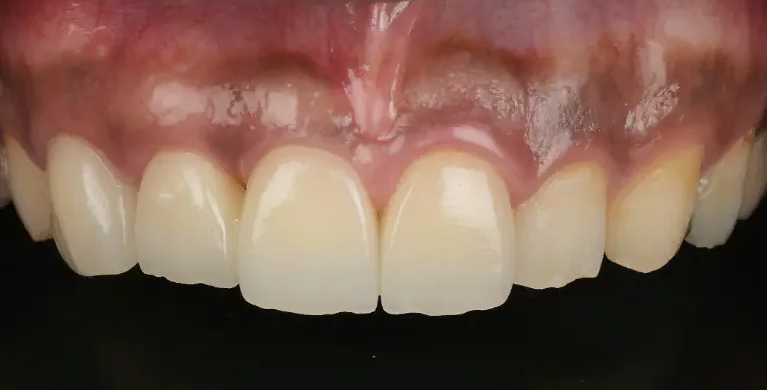

Case1

術前

術後

| 治療名 | GBR、インプラント |

|---|---|

| 治療説明 | インプラント埋入予定部位の骨が大きく吸収していたため、まず骨造成処置を行い、6ヶ月の治癒期間を待った後に骨の増生がされていることを確認しインプラントを埋入しました。2ヶ月間インプラントがくっつくのを待って仮歯を作成し、機能的に問題ないことを確認したうえでセラミックの歯を装着し、見た目と機能を回復しました。 |

| 治療回数・期間 | 8ヶ月 |

| 副作用とリスク | 入れ歯やブリッジと比べ治療期間が長くかかることがあります。骨造成が必要な場合はより長くかかります、インプラント手術後は違和感、痛み、腫れ、出血などが発生する場合があります。一時的なもので、2日〜1週間で治まります。 |

| 料金(税込) | 骨造成:330,000円 インプラント1次手術:220,000円(2本:440,000円) インプラント2次手術:55,000円(2本:110,000円) 上部構造:165,000円(2本:330,000円) 合計:1,210,000円 |